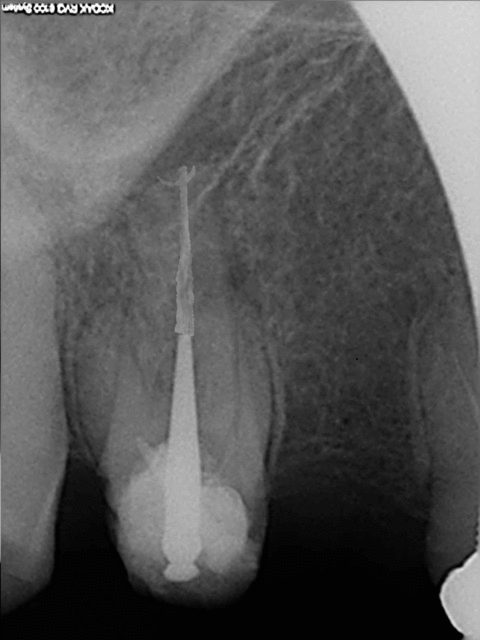

Pas mal photo shop. mais j'ai des progrès à faire. Superbe endo en tout cas vive la vague de gutta chaude. )))))))

C'est un nouveau matériau d'obturation, hyper dense !))))je me suis servi de la gomme. C'est le bordel pour choisir les couleurs.

Celle là est mieux, Comment fait on pour changer les couleurs du crayon ?

R1 modifie  1 qrpbzh - Eugenol

Tu t'es fait chier là. Ca vaut plus que sc 34. Toujours pas rentable l'endo !)))))

Tiens en voila une autre; Tu vas trouver le moyen de faire économiser un spr 57 et spr 50 en plus à la sécu !)))))))

R1 poel1z - Eugenol